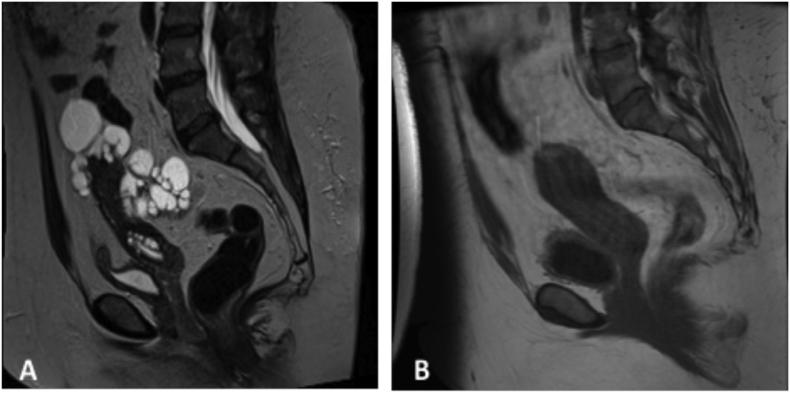

Florid cystic endosalpingiosis with uterine preservation and successful assisted reproductive therapy.

•While endosalpingiosis is often asymptomatic & incidental, florid cystic endosalpingiosis can have a variable presentation•Cystic endosalpingiosis can be difficult to differentiate from other non-neoplastic peritoneal inclusion cysts•Although associated with serous pelvic neoplasms, there is no evidence for oophorectomy at the completion of fertility•There is no strong evidence that hysterectomy along with cyst resection leads to improved outcomes if pathology is benign•This is the first reported case of successful assisted-reproductive therapy after resected florid cystic endosalpingiosis.

•虽然输卵管内膜异位症通常无症状且为偶然发现,但典型的囊性输卵管内膜异位症可有多种表现形式•囊性输卵管内膜异位症可能难以与其他非肿瘤性腹膜包涵囊肿相鉴别•虽然与浆液性盆腔肿瘤有关,但没有证据表明在完成生育后需要切除卵巢•如果病理结果为良性,没有强有力的证据表明子宫切除加囊肿切除能改善预后•这是首例报道的切除典型囊性输卵管内膜异位症后成功进行辅助生殖治疗的病例。